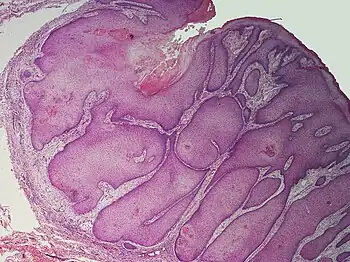

histology